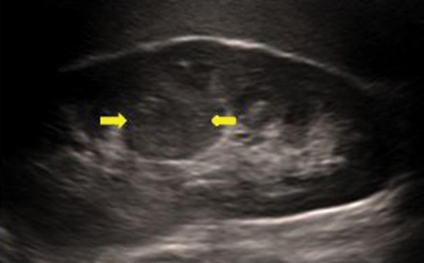

Bladder diverticula